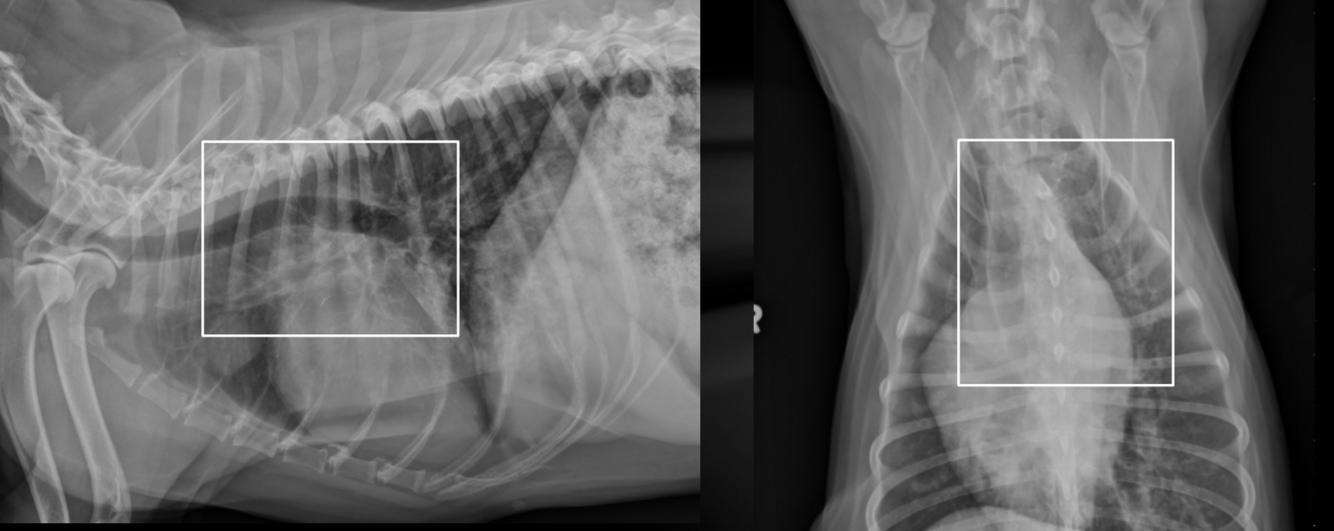

What is shown in these images?

A

tracheobronchial lymphadenopathy

-widening on mainstem bronchi